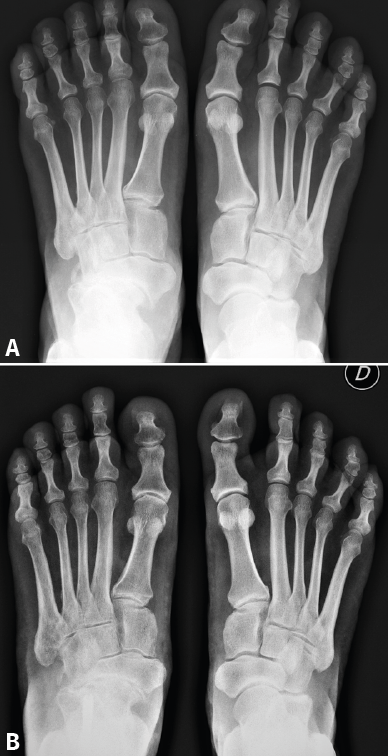

Figura 4. En la proyección radiológica dorsoplantar puede observarse el cambio en la cobertura talonavicular por el desplazamiento del astrágalo antes (A) y un año después de la cirugía (B).

Atendiendo a la clasificación radiológica de Maceira(3), en el preoperatorio encontramos 7 pies (41,2%) en un estadio II, 5 (29,4%) en un estadio III y 5 (29,4%) en un estadio IV. A los 12 meses de la cirugía, se observaron cambios notables en la mayoría de los pacientes, destacando la mejora del aspecto de la artrosis y de la cobertura talonavicular. Tras la cirugía se produjo una regresión en los estadios de Maceira, pasando a tener 6 pies con estadio I (35,3%, ninguno preoperatoriamente), 10 pies con estadio II (58,9%, 7 antes de la cirugía), ningún pie en estadio III (5 antes de la osteotomía) y solo en 1 pie persistió el estadio IV (5,9%, 5 en el preoperatorio) (Figura 3). La mejora de la cobertura talonavicular fue significativa, pasando de una media preoperatoria de − 25,35 (− 17 a − 31) a una postoperatoria de − 15,53 (− 9 a − 26) (Figura 4).